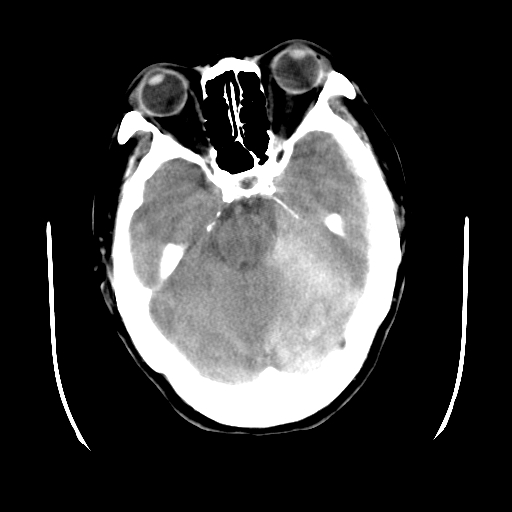

以下是引用gaoshengjiang在2007-10-7 9:18:00的发言:[br]左枕叶脑出血,左额颞顶部及纵裂硬膜下血肿,蛛网膜下腔出血,右颞叶脑梗塞。出血原因:患者年龄较大可能为动脉硬化或血管畸形?建议进一步临床检查。